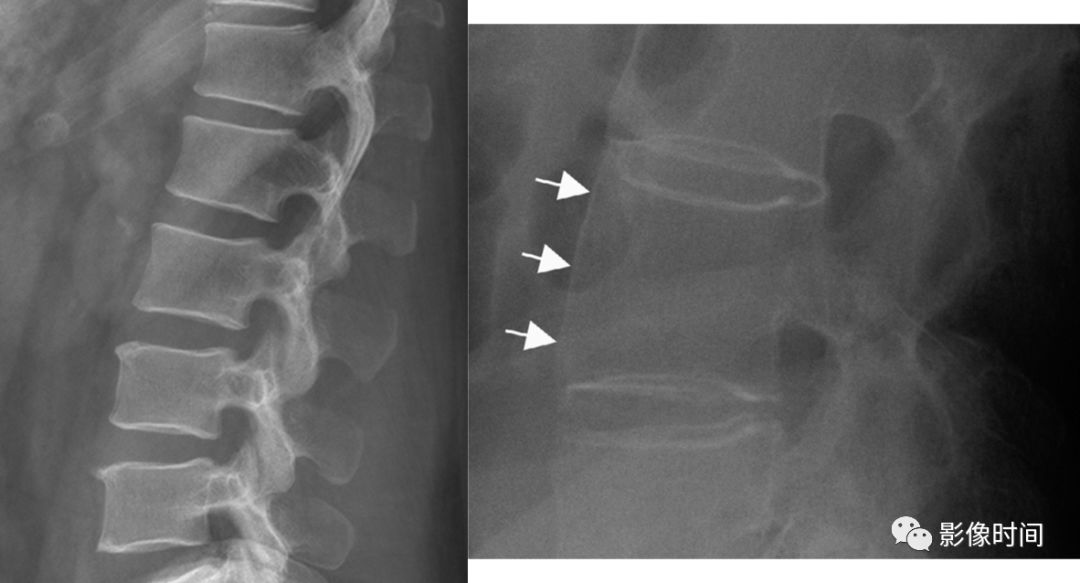

8牙膏征

牙膏征(Toothpaste sign)

牙膏征是指在矢状位脊柱影像中,脱出的椎间盘突入椎管内并向下游走,形似被挤出的牙膏而得名。

典型病例

矢状位 T2WI 像示脱出的椎间盘突入椎管,形似被挤出的牙膏,呈牙膏征(箭示)。